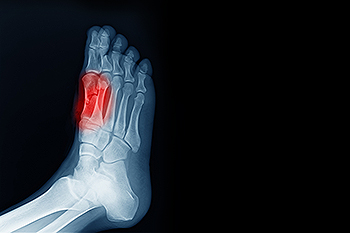

Two tiny bones in the feet located just below the big toe are called the sesamoid bones. The sesamoid bones are at work each time you walk or run, providing leverage to the big toe. When these bones, which are held in place by tendons or embedded in muscle, become irritated, the result is an inflammatory condition known as sesamoiditis. It is considered an overuse injury. People who spend a lot of time on their feet for work, sports, or high-impact activities often incur sesamoiditis. In addition, people with flat feet or high arches may experience this inflammation. Symptoms generally do not emerge suddenly, but instead, develop over a period of time. You may feel intermittent pain in the big toe, notice swelling or bruising in the area, or experience a decrease in the normal functioning of the big toe. Resting the foot often is a good idea, and wearing orthotics in the shoes is another. For more information on how to deal with sesamoiditis, including being fitted for custom orthotics, please consult a podiatrist.

Sesamoiditis is an unpleasant foot condition characterized by pain in the balls of the feet. If you think you’re struggling with sesamoiditis, contact Barry P. Weinstein, DPM of Bellaire Podiatry. Our doctor will treat your condition thoroughly and effectively.

Sesamoiditis

Sesamoiditis is a condition of the foot that affects the ball of the foot. It is more common in younger people than it is in older people. It can also occur with people who have begun a new exercise program, since their bodies are adjusting to the new physical regimen. Pain may also be caused by the inflammation of tendons surrounding the bones. It is important to seek treatment in its early stages because if you ignore the pain, this condition can lead to more serious problems such as severe irritation and bone fractures.

Causes of Sesamoiditis

Treatment for sesamoiditis is non-invasive and simple. Doctors may recommend a strict rest period where the patient forgoes most physical activity. This will help give the patient time to heal their feet through limited activity. For serious cases, it is best to speak with your doctor to determine a treatment option that will help your specific needs.